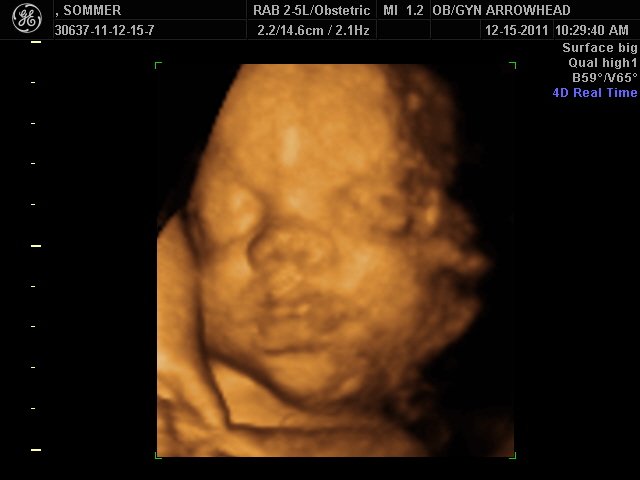

We offer complimentary 3D/4D Ultrasounds to all our OB patients around 30 weeks! The following photos are some examples of our work, shown with permission from our patients.